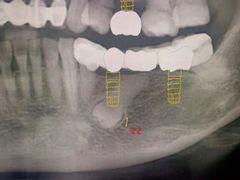

• 牙易美口腔(圣堂店)

• -牙易美口腔(圣堂店)

心觅 | 21-05-16